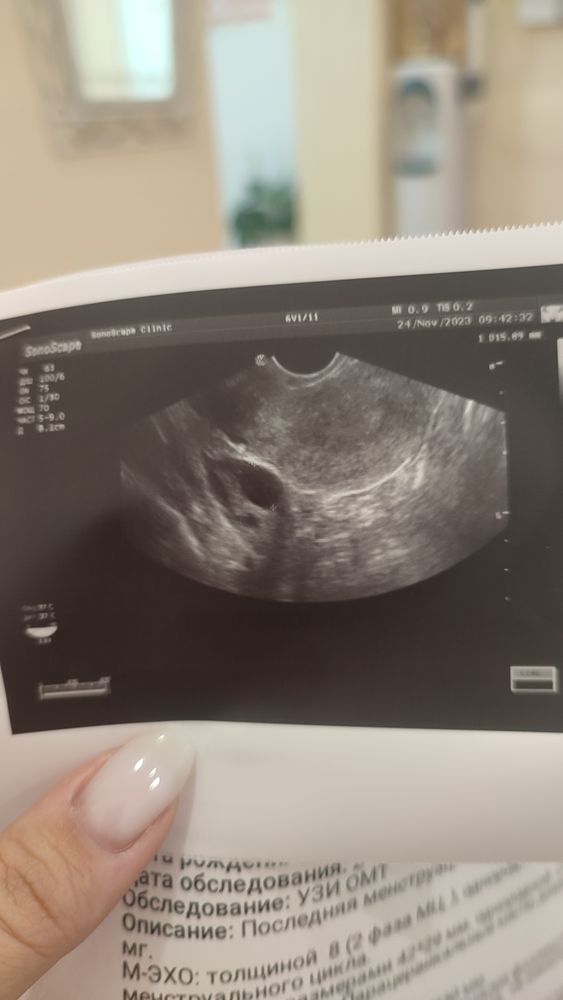

Девочки, я скоро сойду с ума. 4-9 октября прошли месячные, стимуляция кломиком по 50мг, снимки УЗИ от 22,24,27. УЗИ от 22ого показывает фолликул 20. Узи от 24ого у другого врача, где она говорит мне,что доминантный фолликул пошел уменьшаться 16 и овуляции в этом месяце не ждать. При этом на узи 27

ого есть фолликул 24 ,но есть и жидкость за шейкой (фото прикладываю), я не понимаю, у меня уже прошла овуляция,раз есть жидкость или что, но ведь нет жёлтого тела... Помогите пожалуйста разобраться 🙏